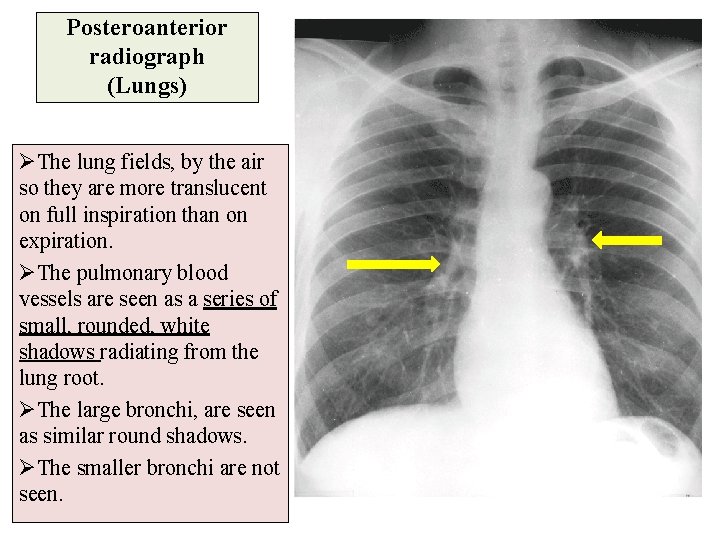

Posteroanterior radiograph (Lungs) ØThe lung fields, by the air so they are more translucent on full inspiration than on expiration. ØThe pulmonary blood vessels are seen as a series of small, rounded, white shadows radiating from the lung root. ØThe large bronchi, are seen as similar round shadows. ØThe smaller bronchi are not seen.